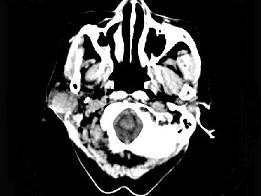

问题 女,72岁,六年前于右面颊部扪及一包块,缓慢增大,其表面较光滑,CT如图所示,该病例应诊断为 ( )

选项 A、颈部淋巴瘤 B、小唾液腺瘤 C、腮腺混合瘤 D、颈部神经纤维瘤 E、Worthin瘤

答案 C